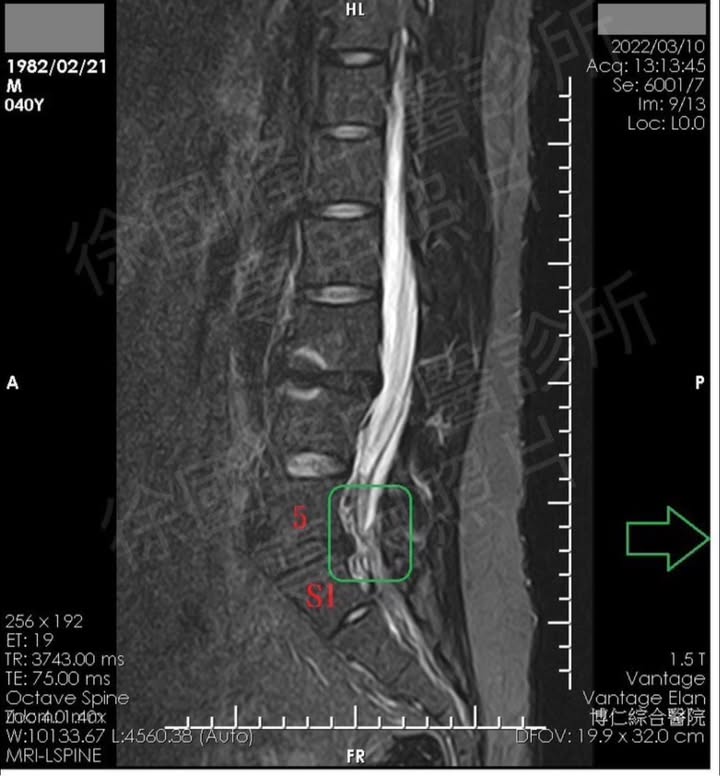

✅患者自述,在還沒來診所就醫前,開車要下車跨門的時候腰就出現強烈的疼痛感,這次因為大痛好幾個月,又去醫院接受核磁共振安排,發現腰椎第五節長骨刺,壓迫神經根,但因為懼怕手術的副作用,從新竹北上就醫。

1.L5S1椎間盤突出

2.梨狀肌症候群